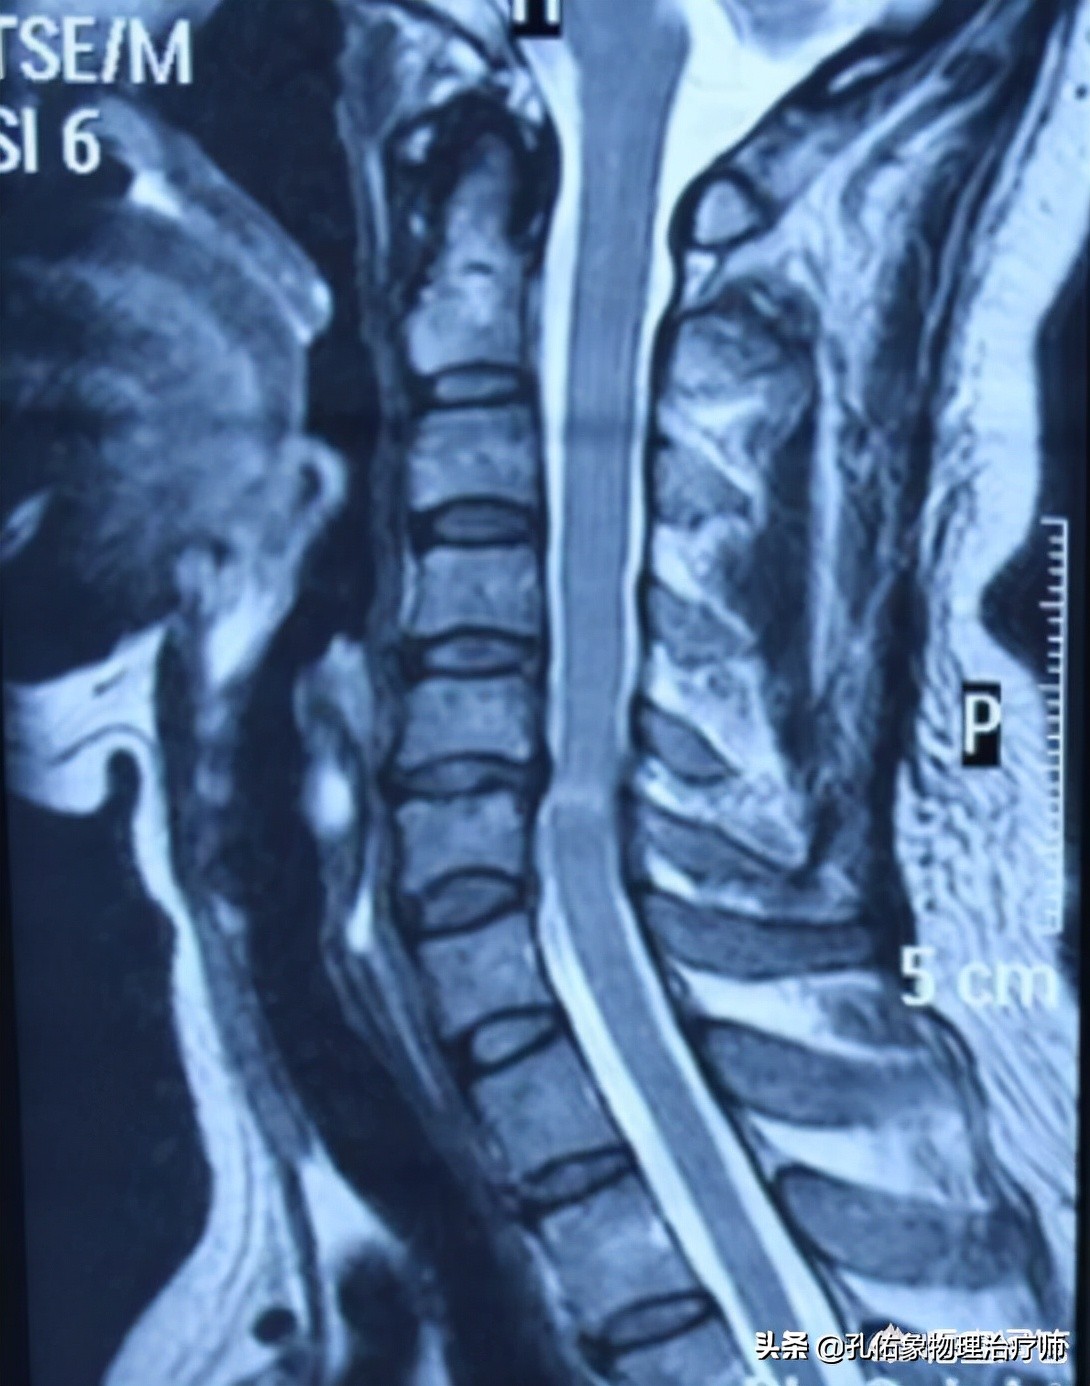

- 脊髓型颈椎病

这类型颈椎病是最严重的,多见于肌肉无力、握力减退、持物容易坠落或双腿发紧,行走困难、步履比较沉重,甚至会出现脚踩棉花的感觉。

主要是因为间盘中央后突、椎体后缘骨赘、增生、肥厚压迫脊髓所致。